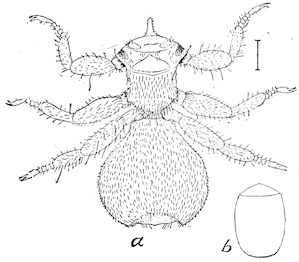

Fig. 2.—Horse suffering from osseous cachexia.

Fig. 3.—Pig suffering from osseous cachexia (fourth stage).

Fig. 4.—Deformity of the face in the horse shown in Fig. 2.

Fig. 5.—Head of a pig suffering from osseous cachexia.

Fig. 6.—Osseous cachexia. This condition developed in two months, the last month of gestation and the first of lactation.

Fig. 7.—Osseous cachexia: softening of the maxillæ.

Fig. 8.—Transverse section through the middle region of the face in a pig suffering from osseous cachexia.